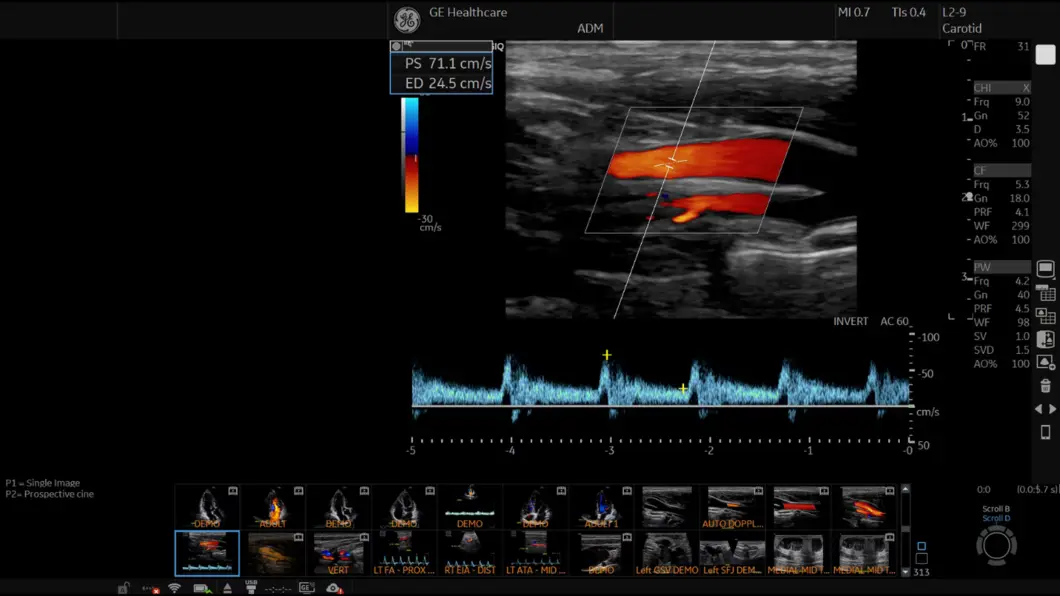

Snažna cSound arhitektura osigurava robusnu i dosljednu izvedbu. Provedite preglede usmjerene na pacijenta i povećajte svoje kliničko povjerenje zahvaljujući izvanrednoj vaskularnoj osjetljivosti sustava.

Naša moćna cSound™ arhitektura povećava snagu obrade i protok podataka kombiniranjem XDclear™ sondi i cSound Imageformer-a s naprednom tehnologijom Speckle Reduction Imaging (SRI). Rezultat je iznimna kvaliteta slike, jasnoća i klinička pouzdanost u širokom rasponu kliničkih primjena.

Inteligentne značajke kao što su 2D Shear Wave Elastography, Measure Assistant i Radiantflow™ smanjuju potrebu za invazivnim postupcima pružajući dodatne, vrijedne podatke za informirano donošenje odluka.